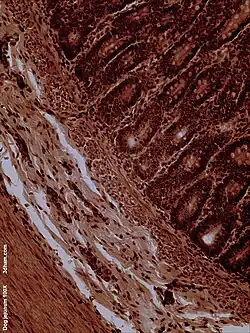

Histology

The jejunum contains very few Brunner's glands (found in the duodenum) or Peyer's patches (found in the ileum). However, there are a few jejunal lymph nodes suspended in its mesentery. The jejunum has many large circular folds in its submucosa called plicae circulares that increase the surface area for nutrient absorption. The plicae circulares are best developed in the jejunum.

There is no line of demarcation between the jejunum and the ileum. However, there are subtle histological differences:

• The jejunum has less fat inside its mesentery than the ileum.

• The jejunum is typically of larger diameter than the ileum.

• The villi of the jejunum look like long, finger-like projections, and are a histologically identifiable structure.

• While the length of the entire intestinal tract contains lymphoid tissue, only the ileum has abundant Peyer's patches, which are unencapsulated lymphoid nodules that contain large numbers of lymphocytes and immune cells, like microfold cells.